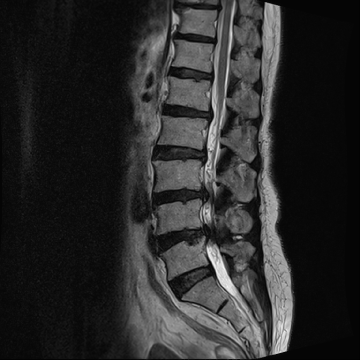

요추 협착증 수술 전·후

2020.08.30

2022.09.06

ㆍ환자 동의를 받은 자료이며, 이미지 사진은 실물과 다를 수 있습니다.

ㆍ모든 자료는 새움병원 자료입니다.